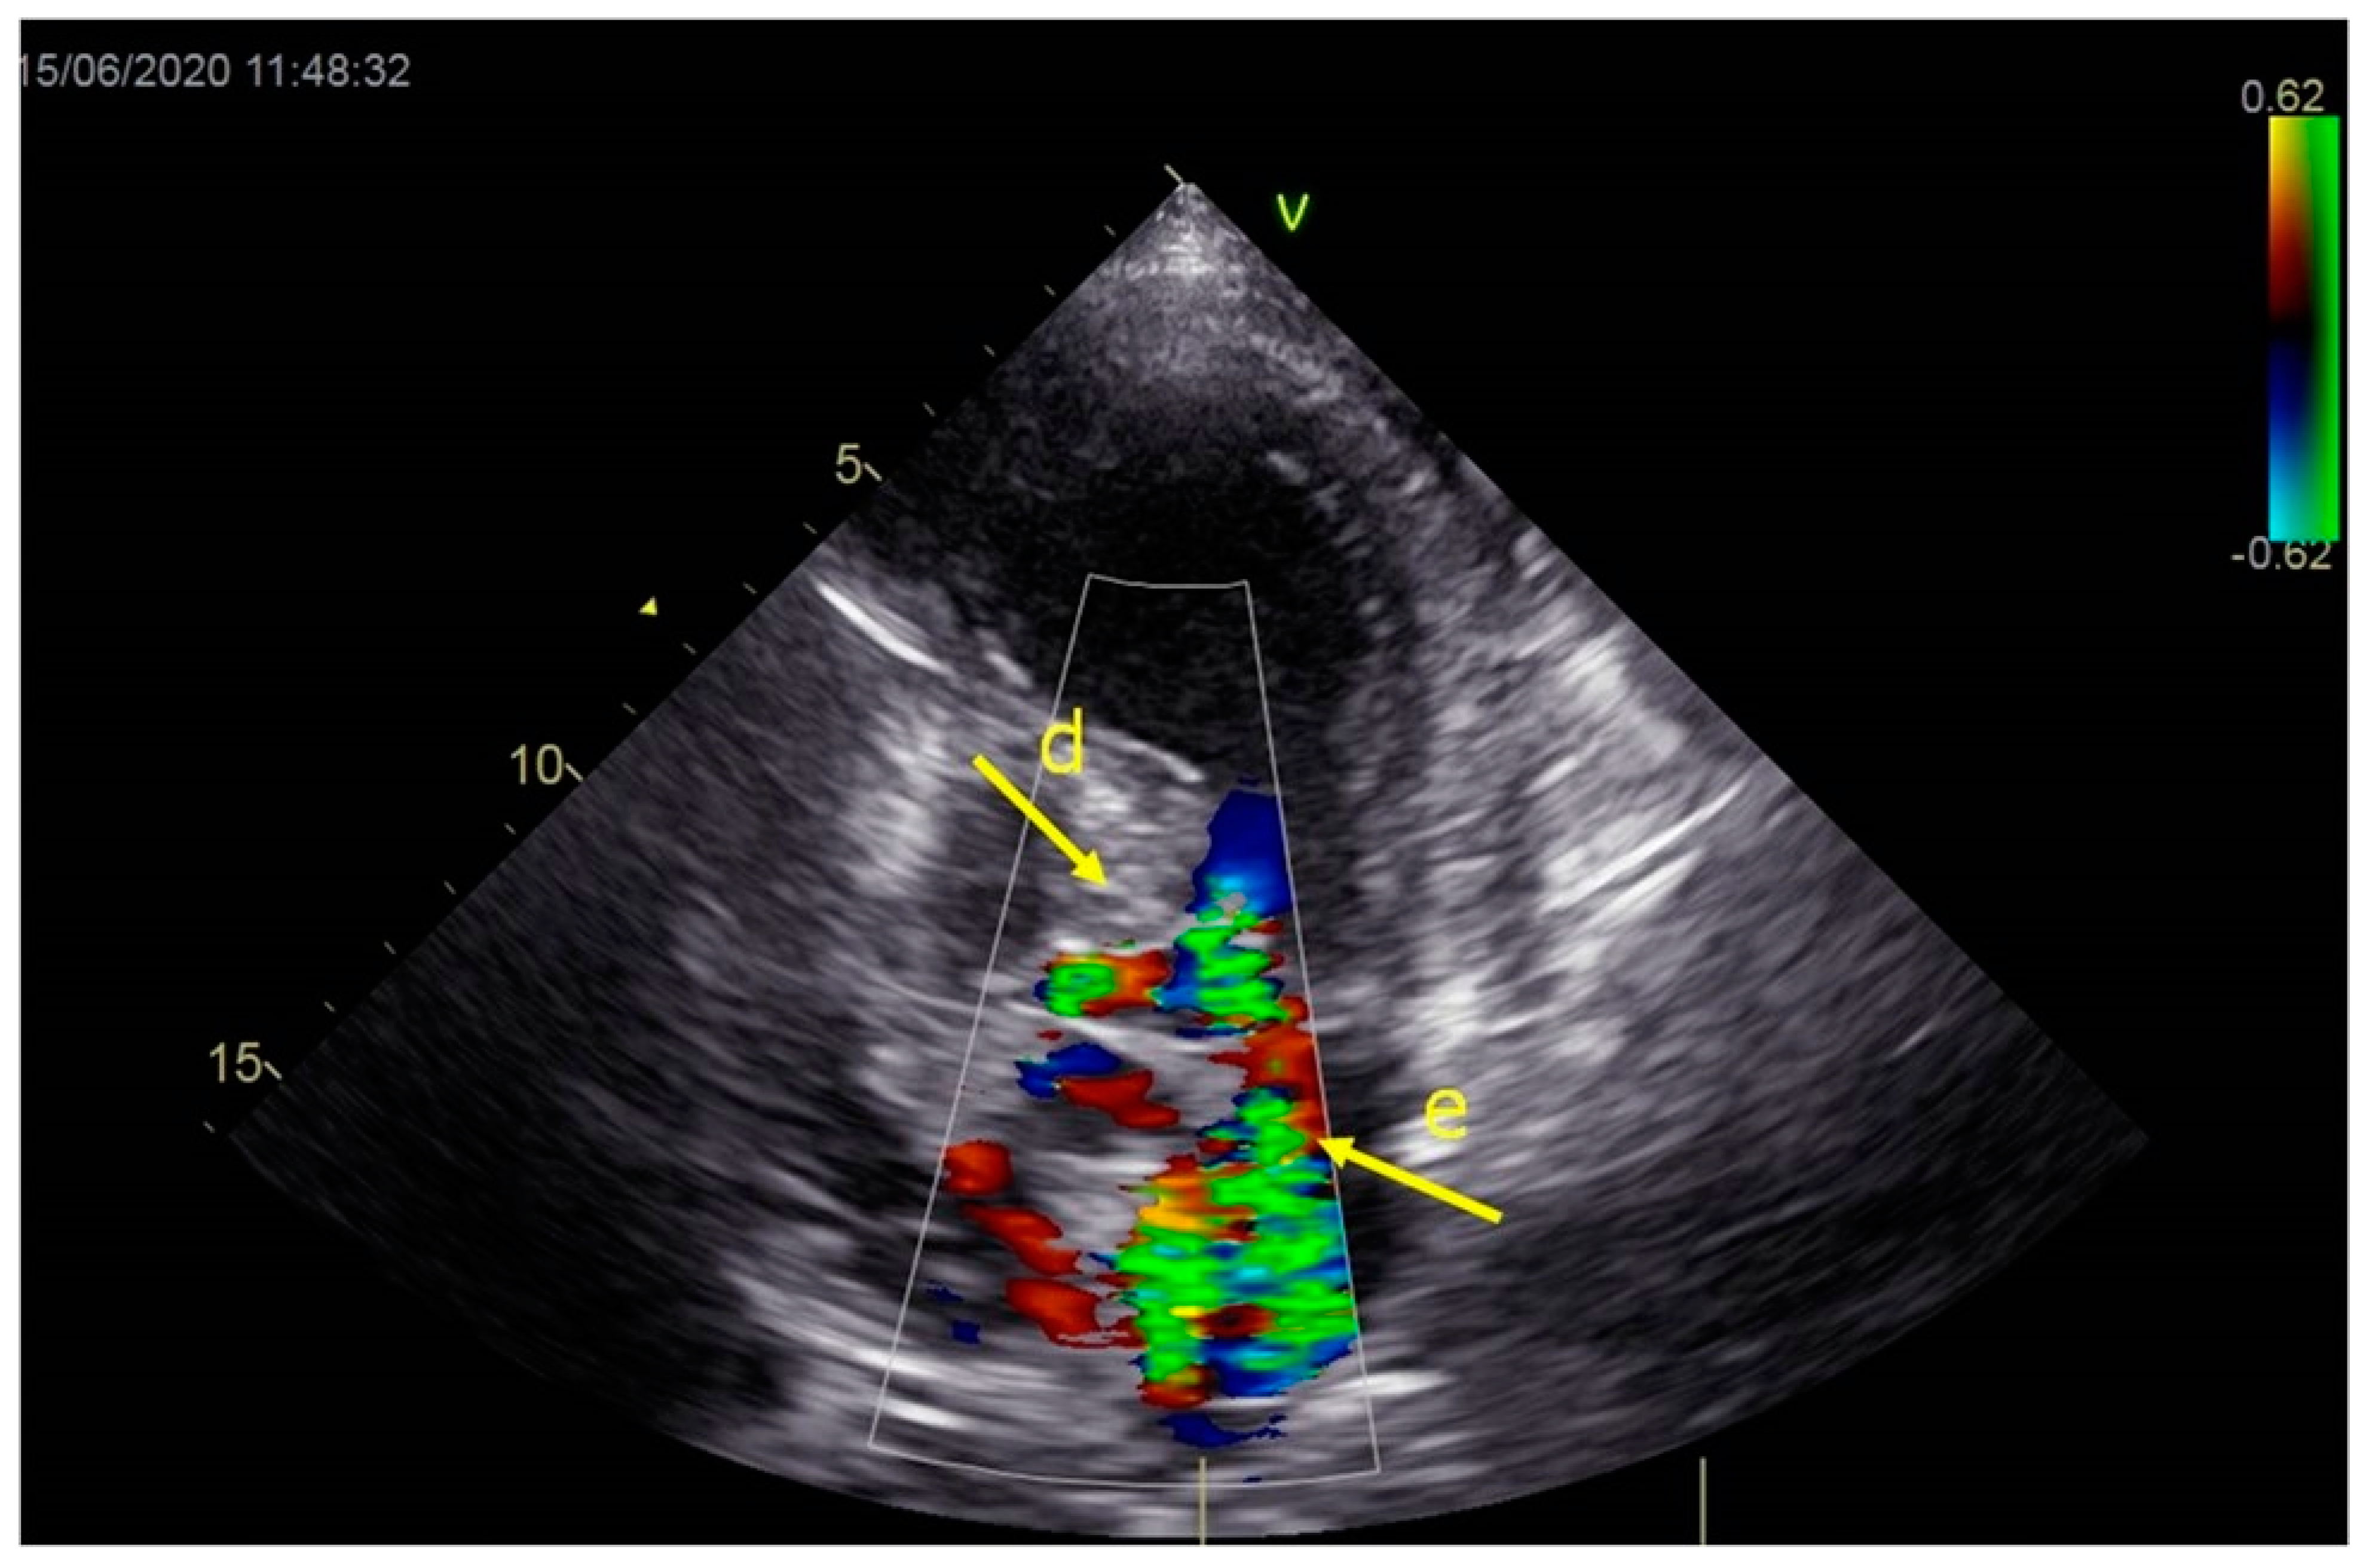

As a result, the patient was referred to a specialized medical institution. Upon admission, the patient was conscious, confused, hypotensive (TA 80/50 mmHg), with a heart rate of about 110/min, and showing clinical signs of hypoperfusion and cardiogenic shock, Killip IV. The medical staff administered sedation, inserted an endotracheal tube, and placed her on invasive mechanical ventilation. The patient was given crystalline solutions, inotrope, and vasopressor medication. An urgent echocardiographic examination was performed due to a rough systolic murmur over the precordium. It revealed akinesia of all medioapical segments of the left ventricle and akinesia basally inferior, where the myocardium was fibrously altered. Other hyperkinetic basal segments formed a dynamic obstruction of the left ventricular outflow tract (LVOTO) with turbulent flow and moderate mitral regurgitation (Figure 2 and Figure 3). The maximum gradient above the LVOT was 160 mmHg (Figure 4). The aortic valve area was 1.8 cm2 (Figure 5). The ejection fraction of the left ventricle (LVEF) was estimated to be 25%. The examination also revealed pericardial effusion with separation between pericardial layers along the right ventricle and atrium of up to 1.2 cm, but without any signs of tamponade.

Figure 3.

Echocardiography registered moderate mitral regurgitation (d—LVOT, e—mitral regurgitation).